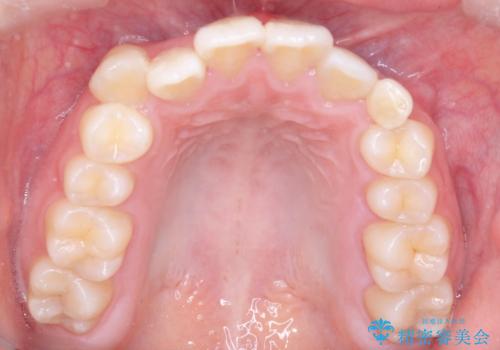

- 八重歯を主訴に来院されました。

左側犬歯が埋伏していましたが、第一小臼歯(4番目の歯)を抜歯したことでできたスペースに牽引し、右側の飛び出した八重歯を含め、歯全体を整列することができ患者様も満足していただきました。